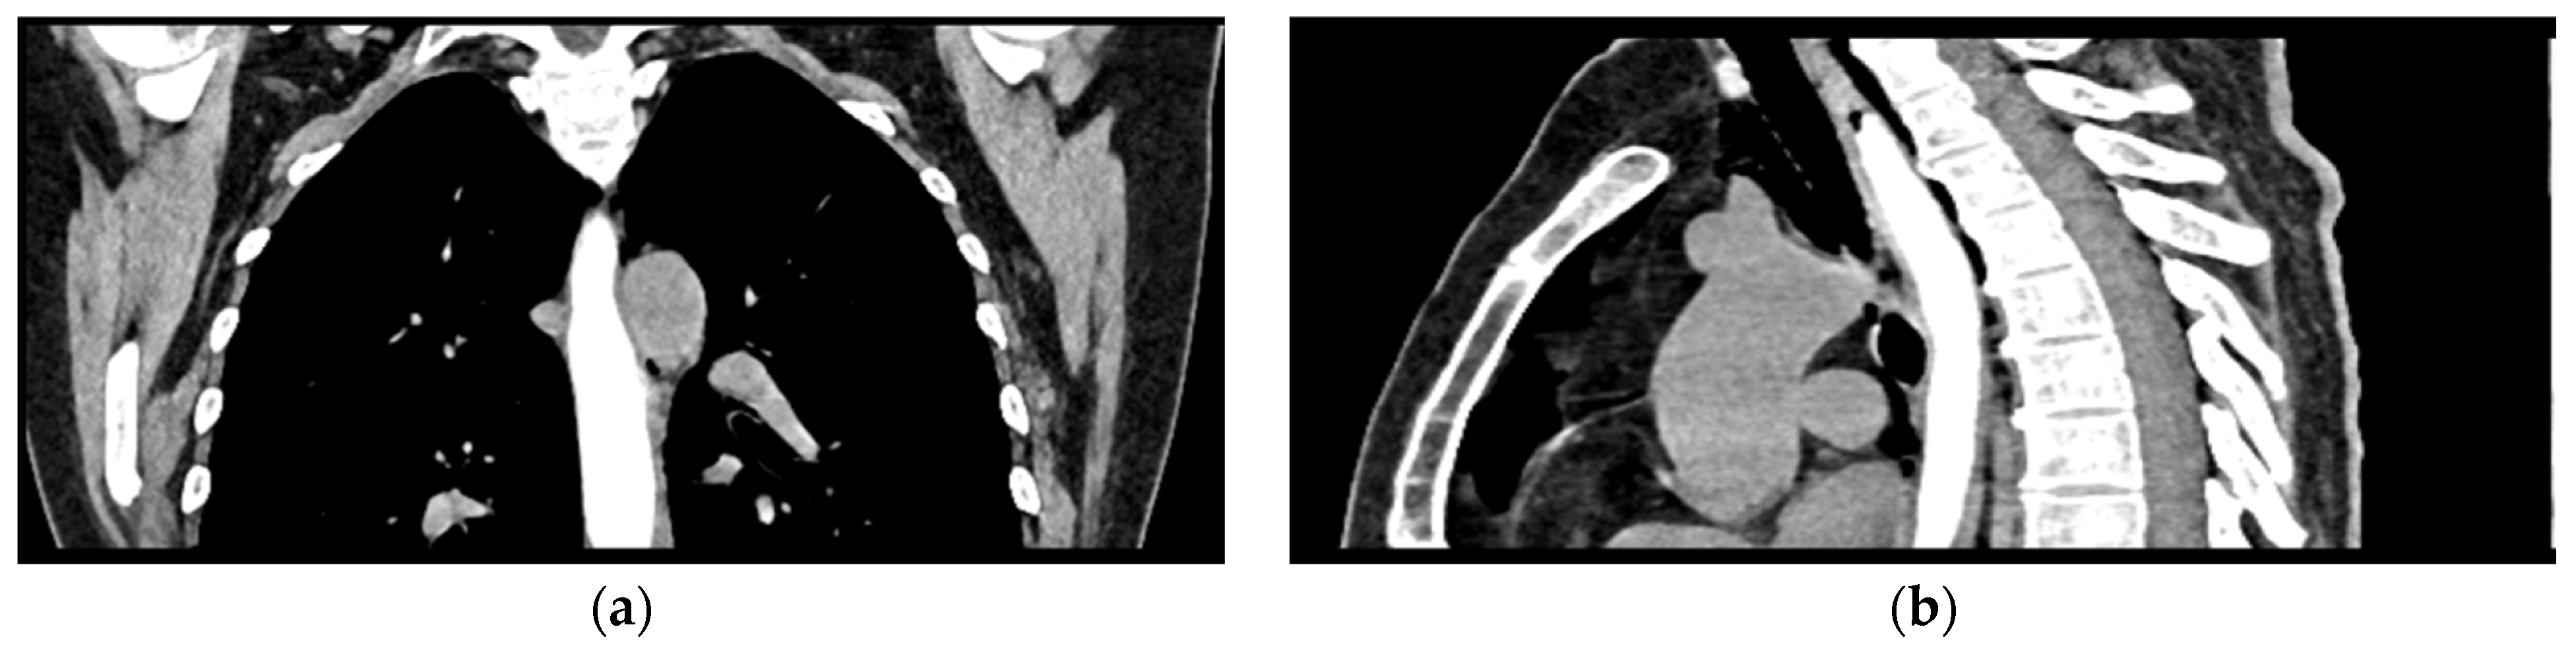

Given the patient’s history of vomiting, and consulting with the thoracic surgeon, a second CT scan with oral contrast was performed approximately 3 h later, after initial stabilization of the patient, to rule out an esophageal rupture. The subsequent imaging revealed the progression of the pneumomediastinum, with increased extension into the cervical region, including the peritracheoesophageal, perithyroidal and retropharyngeal spaces (Figure 3), without evidence of esophageal rupture (Figure 4). Oxygen therapy and empiric antibiotic therapy were initiated in the ED as initial treatments of this condition.

Figure 4.

Oral contrast chest CT scan with intact esophageal contour and no extravasation of the contrast substance: (a) coronal view; (b) sagittal view.

The patient was referred to diabetology in order to be admitted to hospital. Although the patient presented a good clinical and biological evolution, her condition deteriorated after about 12 h; therefore, another chest CT scan was performed, revealing extension of the pneumomediastinum in comparison to the prior scan and the presence of an additional left pneumothorax measuring approximately 7 mm (Figure 5).

Figure 5.

Chest CT showing the presence of pneumothorax (arrows): (a) axial view; (b) coronal view.